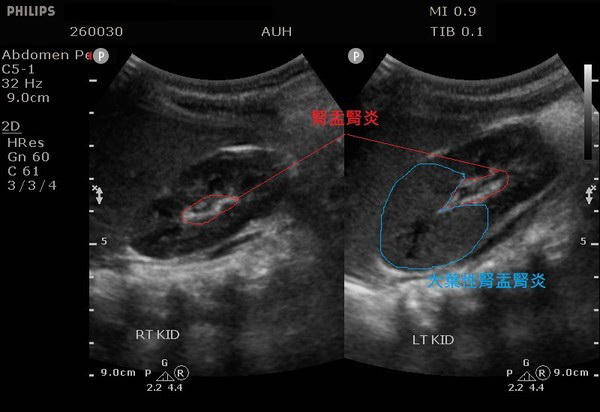

医师安排超音波检查后,发现黄小弟的双侧肾盂肾炎、左肾前端实质发炎,经尿液培养后终于确诊为大肠杆菌引起的左侧“急性大叶性肾盂肾炎”、及双侧“急性肾盂肾炎”,经静脉注射抗生素治疗7天才顺利出院,但出院后仍需使用抗生素治疗3周以上。